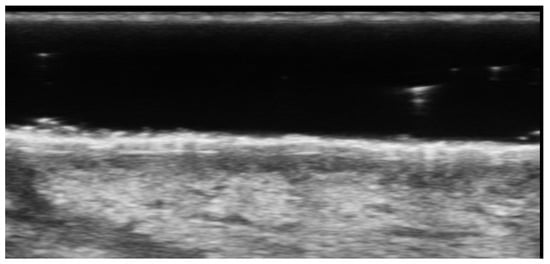

- Gonzalez, C.; Wortsman, X. How to Start on Dermatologic Ultrasound: Basic Anatomical Concepts, Guidelines, Technical Considerations, and Best Tips. Semin. Ultrasound CT MRI 2024, 45, 180–191. [Google Scholar] [CrossRef] [PubMed]